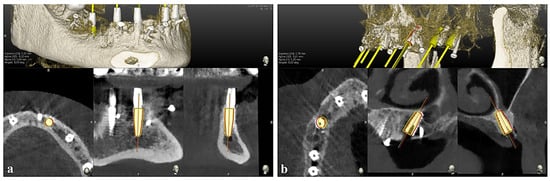

2.5. Placement Accuracy Evaluation

The assessment of placement accuracy was determined by overlapping the preoperative CBCT with planned implants and the postoperative CBCT with placed implants using EvaluNav software 1.3.6 provided by the Navident navigation system (Claronav Inc., Toronto, ON, Canada). Calibration and registration were performed directly between the two volumetric images. The software offers various visualization tools that verify or enhance the precise alignment of the two CBCTs. Once the surgeon is satisfied with the volumetric registration, the software automatically matches the planned implant shape onto the postoperative image and calculates deviations between the planned and actual implant locations (Figure 3).

To address this study’s primary goal, the accuracy of implant placement was evaluated in terms of deviation at the coronal/entry (ENTRY 2D), apical (APEX 3D), vertical/depth (VERTICAL APEX), and angular (ANGLE) levels. Subsequently, the differences in deviation were compared between implants placed in the mandible and maxilla, the anterior and posterior regions of both arches, the healed and post-extraction sites, and among the various bone densities.

Figure 3. Matching the implant model with the postoperative CBCT and measuring the deviation using a corrected angular axis between the planned and actual implant positions with the accuracy evaluation software in (a) the mandible and (b) the maxilla.